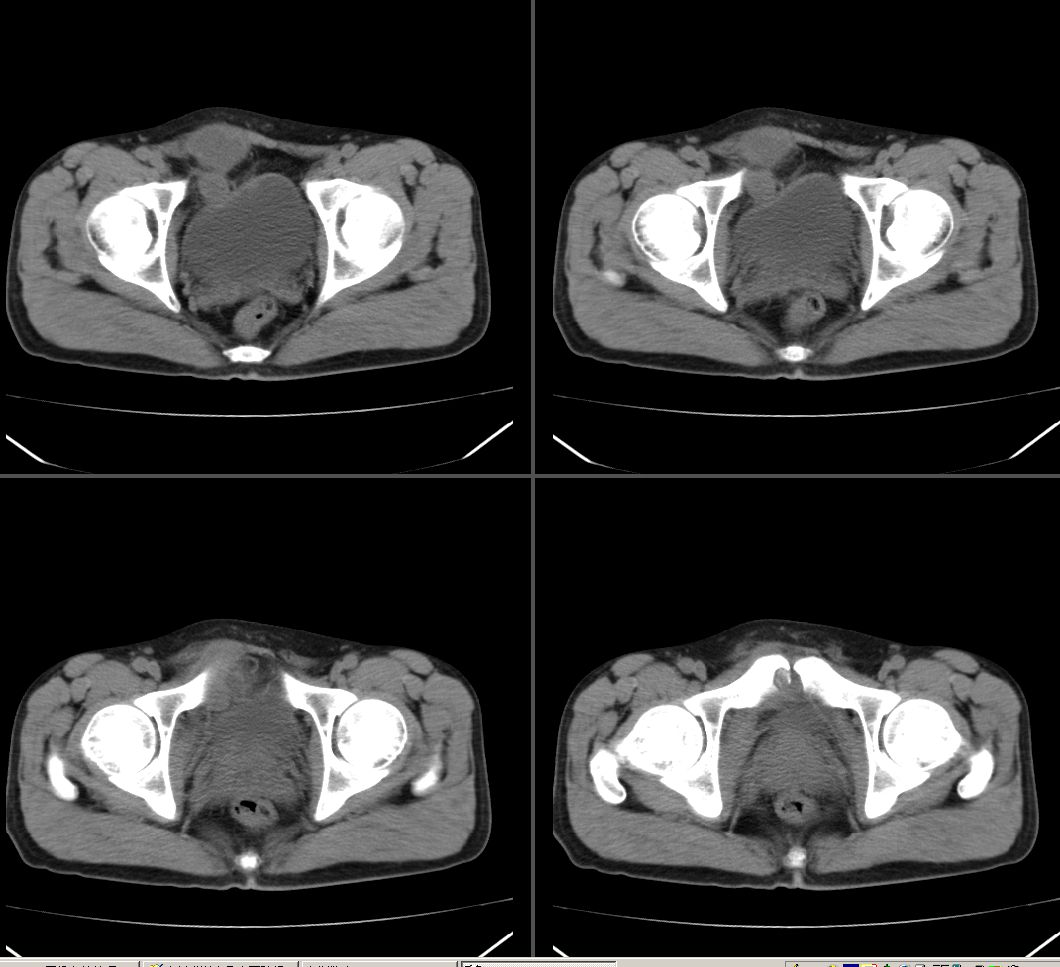

右腹直肌腱鞘来源,韧带样纤维瘤可能性大,病变有侵袭性,右侧耻骨联合有骨质缺损。

鉴别:肌纤维瘤样增生,神经源性病变。

前腹壁肿块,囊性变,右侧耻骨联合有骨质缺损。

考虑神经源性肿瘤,神经鞘瘤

右腹直肌腱鞘来源,耻骨联合有骨质缺损,考虑神经源性肿瘤

考虑 1脐尿管囊肿 2神经鞘瘤囊变。